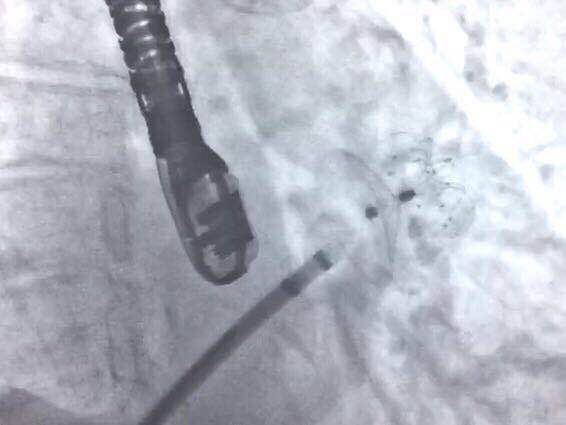

造影检查封堵效果

封堵器释放后造影